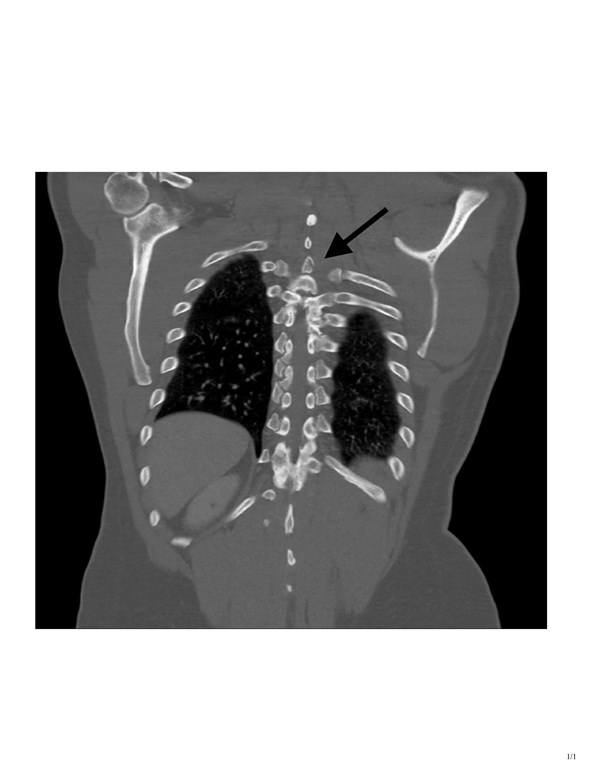

CT imaging showed a T3 spinous process fracture raising concern for intracanal blood products and possible cord injury. MRI later that night confirmed cord contusion with possible injury to the right hemi cord, and dorsal epidural hematoma extending from T2 to T10.

At the time of presentation, we knew the patient displayed clinical signs of Brown-Séquard, and the CT showed injury on the right side of the cord. What was unclear at the time was whether the patient had a true hemi-section of the spinal cord, leading to permanent disability, or if he was instead suffering from a transitory spinal shock due to swelling and hematoma.

An MRI obtained the next day confirmed right-sided spinal cord hemi-section, as well as associated cord contusion and epidural hematoma. Additionally, when the patient was discharged from the Shock Trauma ICU several days later, he was still exhibiting the same neurological deficits. The patient was discharged directly to a rehabilitation center, where occupational and physical therapists were expected to help him maximize his recovery and learn to live with his new deficits.